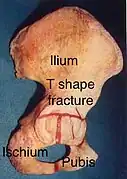

T shape fracture shown on bone model

T shape fracture shown on bone model -

X-ray of T shape fracture

X-ray of T shape fracture

| Posterior wall | This is the most common variety of acetabular fracture. It typically occurs due to dashboard injury; when a person travelling in a vehicle involved in a head-on collision, the force applied over the flexed knee travels along the femur bone to the head of the femur, breaking the posterior wall of the acetabulum. The head of the femur is dislocated outside the joint. | T shape | When a transverse fracture also had a vertical fracture line, it is called a T shape fracture. Here the innominate bone is broken in such a way that all three parts of it, the ilium, the ischium and the pubis are separated from one another. This is a three part fracture. Though both columns are broken, the weight bearing dome is still attached to the main part of the ilium and hence it is not a true fracture of both columns.

This fracture may be associated with a fracture through the posterior wall as well, making it more complex. This fracture typically occurs when the injuring force is applied from the side, against the greater trochanter of the femur, as in a fall on the side or being hit on the side. This force may be combined with dashboard injury as well. The fracture is best seen in anteroposterior view and iliac and obturator oblique views. |